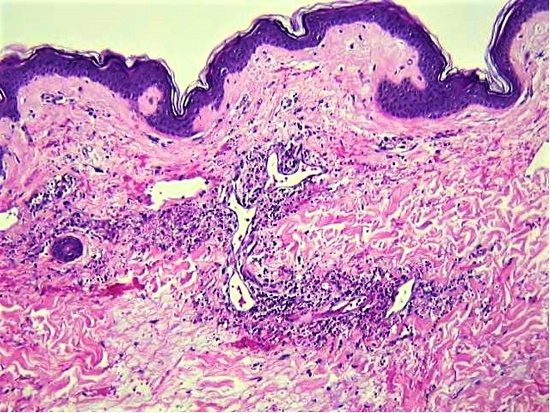

Autopsy also revealed leukocytoclastic vasculitis involving arterioles, capillaries and venules in the skin (Figure 3).

Treatment and prognosis of vasculitis depend on what type of vasculitis an individual patient has, but individual cases of vasculitis are often difficult to classify.5 Our case illustrates this aspect of vasculitis. The 2012 revised international Chapel Hill consensus conference nomenclature of vasculitides provides definitions of the types of vasculitis.6 This nomenclature has Takayasu arteritis and giant cell arteritis as the only two types of large vessel vasculitis, polyarteritis nodosa and Kawasaki disease as the only two types of medium vessel vasculitis, and then 7 types of small vessel vasculitis, divided into those associated with antineutrophil cytoplasmic antibodies and those with immune complexes.6 Polyarteritis nodosa is defined as a necrotizing arteritis of medium or small arteries without glomerulonephritis or vasculitis in arterioles, capillaries or venules, and not associated with antineutrophil cytoplasmic antibodies (ANCAs).6 Our case had necrotizing arteritis involving predominantly medium arteries without glomerulonephritis or ANCA, but also leukocytoclastic vasculitis involving arterioles, capillaries and venules in the skin, which excludes it from the definition of polyarteritis nodosa.

The 2012 revised international Chapel Hill consensus conference nomenclature of vasculitides has a category called vasculitis associated with probable etiology and lists cancer-associated vasculitis in this category without describing this entity.6 The complete autopsy in this case revealed an unsuspected small (0.6 cm) invasive adenocarcinoma of the colon, so this might be a cancer-associated vasculitis. Malignant tumors are sometimes an immunological trigger resulting in an autoimmune vasculitis. In a study of 60 patients with cancer-associated vasculitis, 23% had vasculitis diagnosed before the malignancy (an average of one year prior), 38% had vasculitis and malignancy diagnosed concurrently, and 5% had the vasculitis treated effectively by surgical excision of the cancer.7 Few of the 60 patients in that study, however, had surgically removable tumor; 63% had hematologic malignancies and only 37% had solid tumors.7 In a study of 15 patients limited to those with solid tumors and paraneoplastic vasculitis, 53% had complete resolution of vasculitis after tumor removal and 27% had complete resolution of vasculitis after successful cytotoxic chemotherapy for the malignancy.8 Our patient had cutaneous leukocytoclastic vasculitis; this is the most common type of vasculitis associated with cancer.7,8 Consideration of the possibility of an occult malignancy is important in older adult patients who present with vasculitis, especially leukocytoclastic vasculitis of the skin.